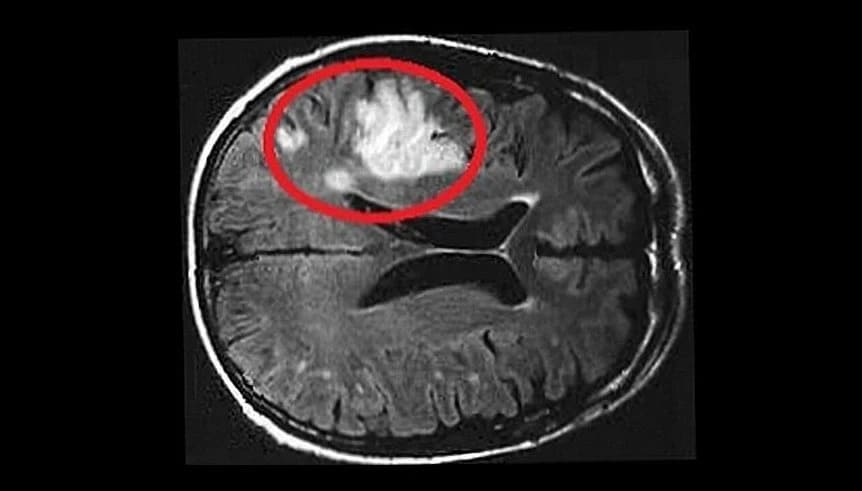

Ein Schlaganfall ist die Folge einer Durchblutungsstörung oder Blutung im Gehirn. Durch diese Vorgänge erhalten Nervenzellen im Gehirn zu wenig Sauerstoff und Nährstoffe und gehen zu Grunde. Dies kann zu einem anhaltenden Ausfall von Gehirnfunktionen und in der Folge zu Sprachstörungen, Sehstörungen und Lähmungen führen. Weitere Warnzeichen sind Schwindel, Gleichgewichts- oder Koordinationsstörungen, Gefühlsstörungen (häufig in Arm und Bein derselben Körperseite) und Doppelbilder. Üblicherweise treten bei einem Schlaganfall nur einige wenige dieser Beschwerden auf – welche, hängt davon ab, welche Teile des Gehirns betroffen sind. Die Beschwerden beginnen üblicherweise aber nicht immer plötzlich (‘schlagartig’, daher der Name der Erkrankung).

Man unterscheidet beim Schlaganfall zwei Formen: den häufigeren ischämischen Schlaganfall, der durch einen Gefäßverschluss entsteht (80% der Fälle), und den selteneren hämorrhagischen Schlaganfall, der durch eine Hirnblutung hervorgerufen wird (20% der Fälle). Jede dieser Formen kann verschiedene Ursachen haben die gewissenhaft abzuklären sind.